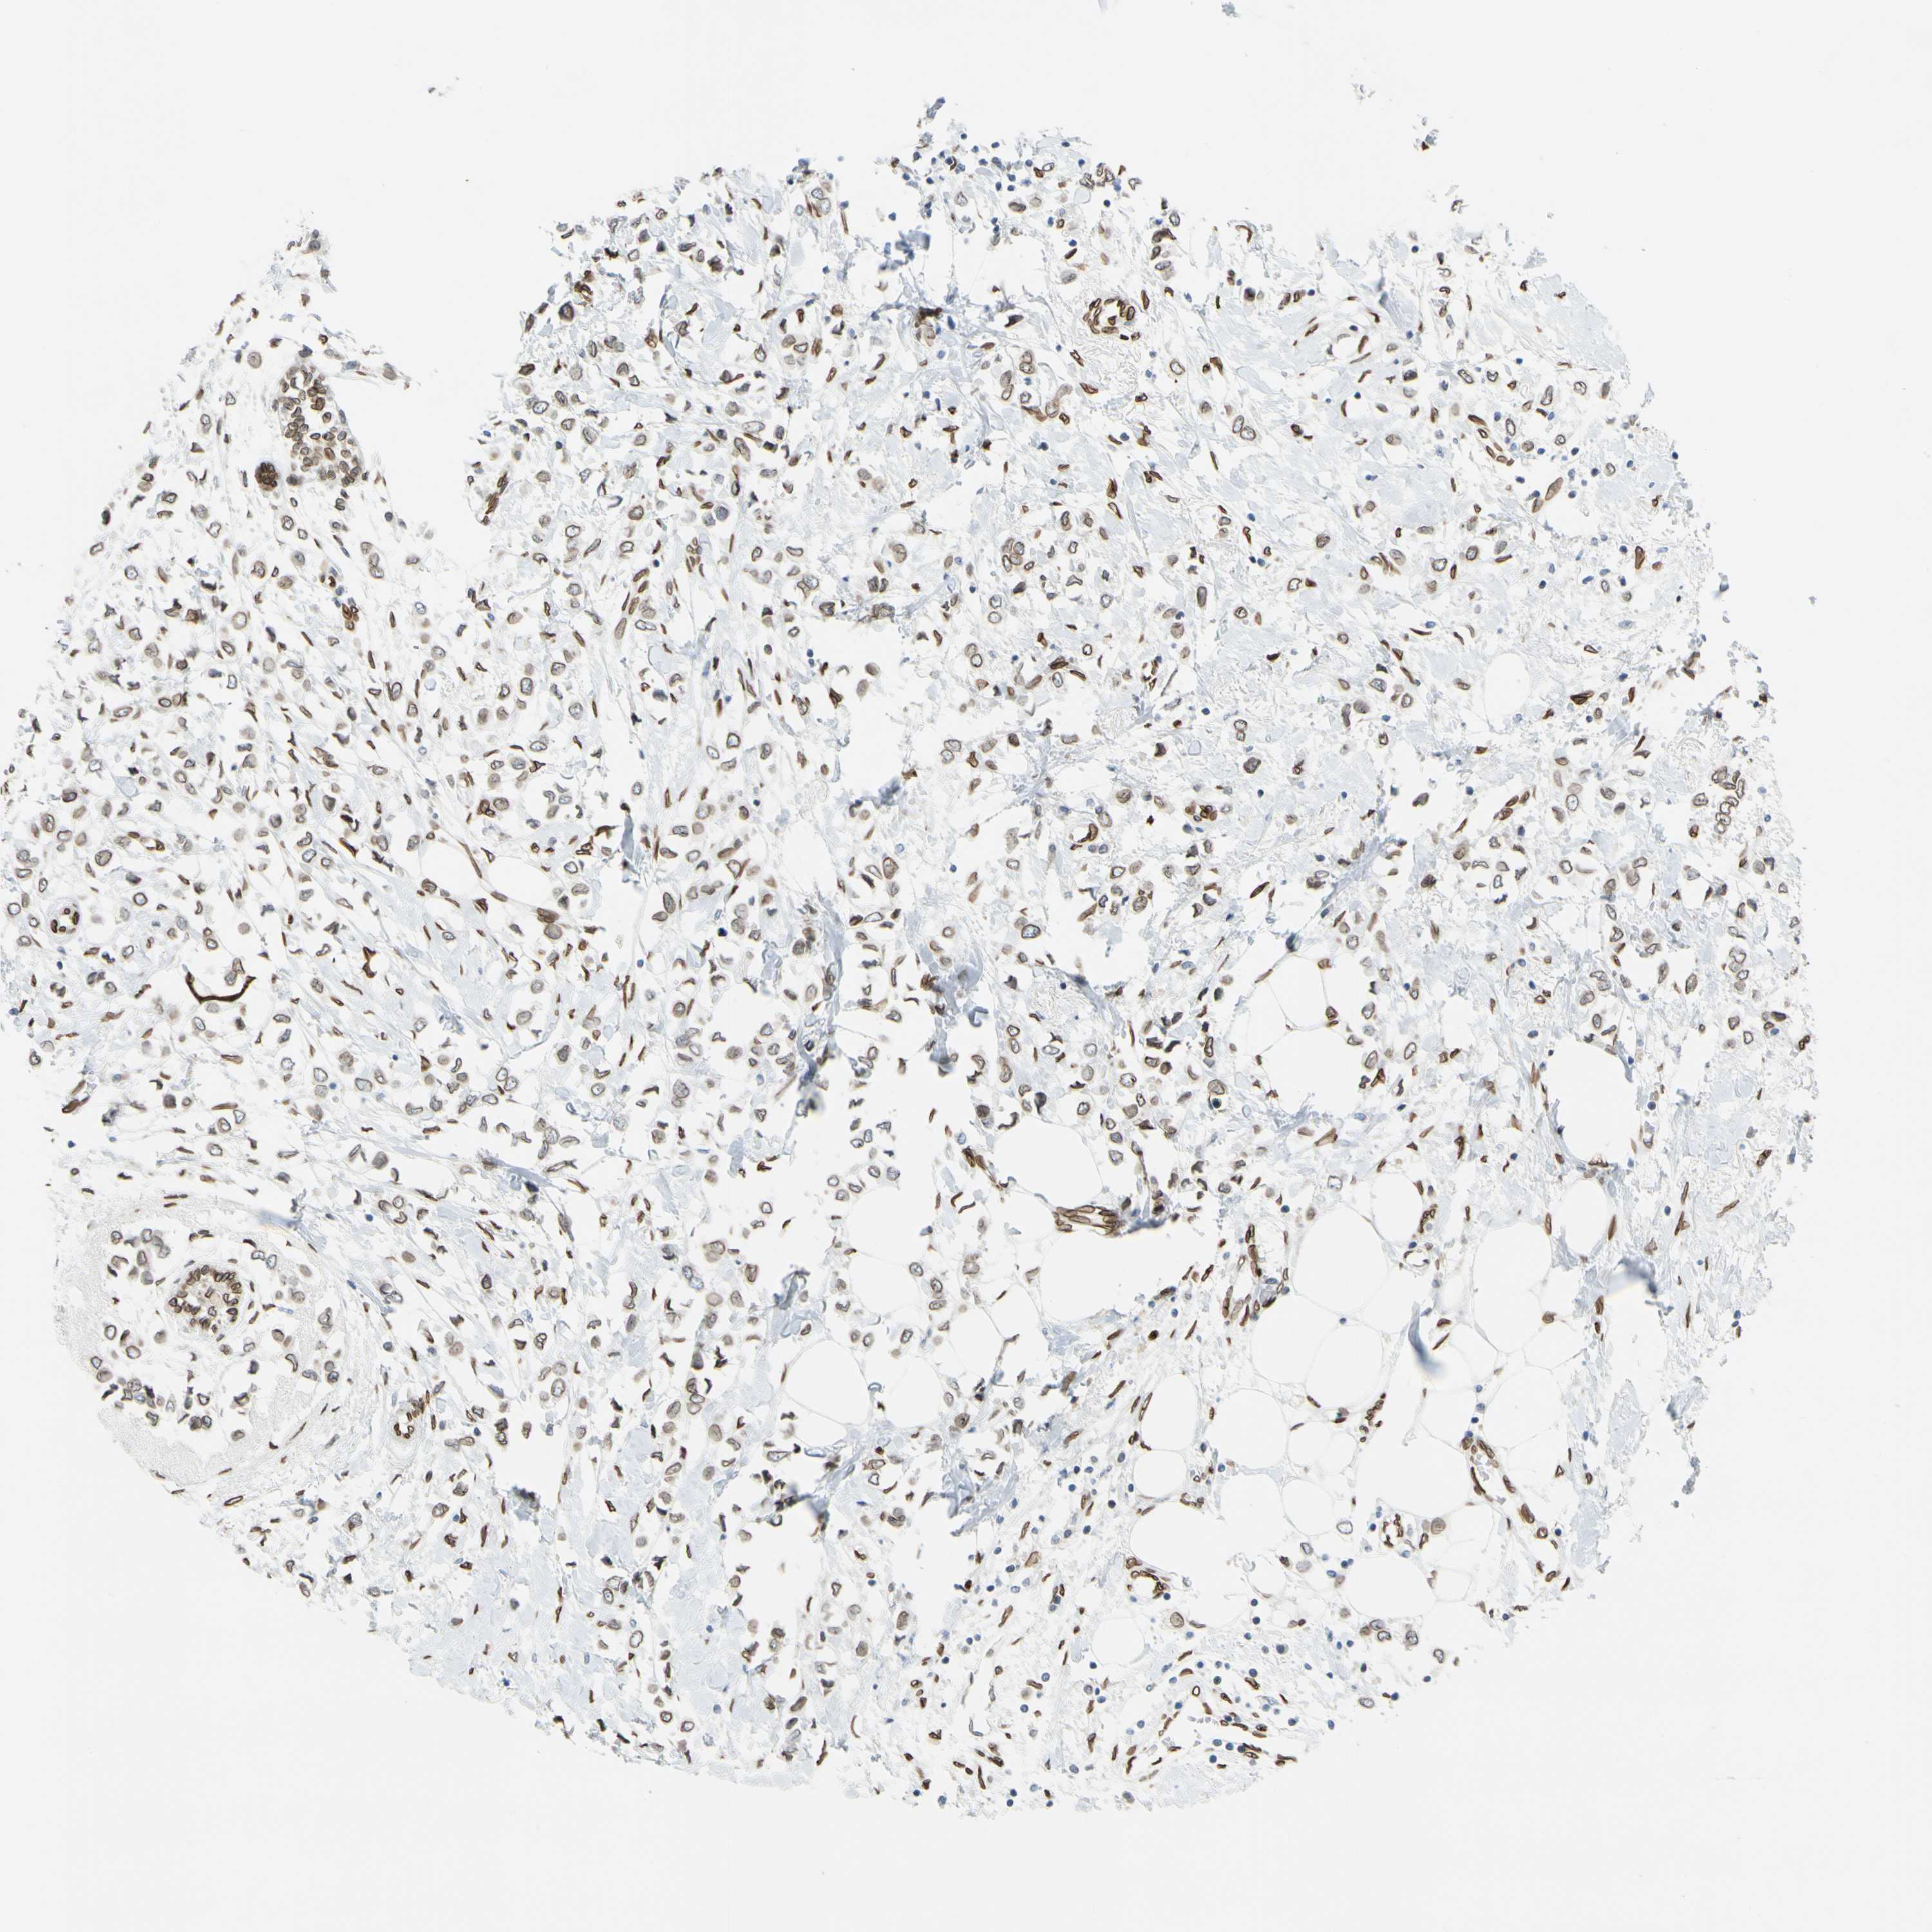

CANCER BREAST CANCER Show tissue menu

BRCA TCGA BRCA VALIDATION PROTEIN EXPRESSION

SUN1 is not prognostic in Breast Invasive Carcinoma (TCGA)